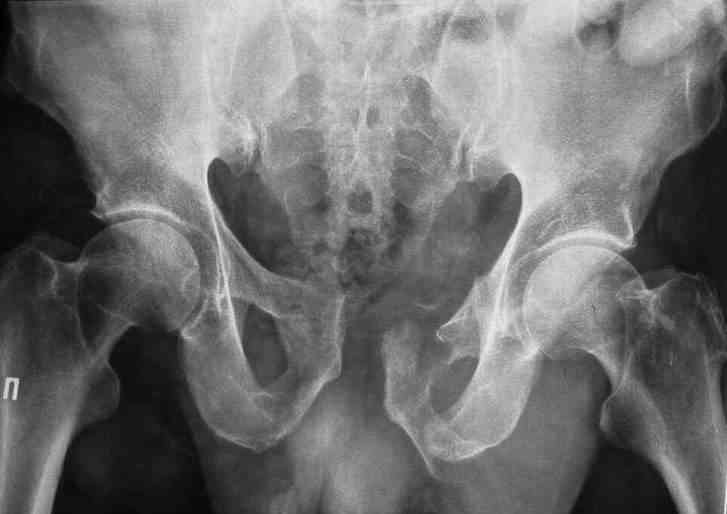

Уважаемые коллеги.У больного оскольчатые переломы левых лонной и седалищной костей со смещением, разрывом симфиза и распространением линии перелома на вертлужную впадину; переломы крыла левой подвздошной кости и правой боковой массы крестца без смещения; разрыв уретры.За последние годы пациент 6 раз оперирован на передней брюшной стенке (гнойный аппендицит срединным доступом, вентральная послеоперационная грыжа и паховые грыжи с обеих сторон, оперированные по 2 раза каждая). Остались 3 грубых втянутых рубца после этих операций. В настоящее время имеются 2-сторонние паховомошоночные грыжи (на одной из КТ-грамм указаны стрелками), из которых левая - значительных размеров. Мошонка огромная, однако, не напряженная. Состояние больного на сегодняшний день относительно удовлетворительное, кровопотеря компенсирована, мочевой пузырь катетеризирован.Прошу мнения сообщества по следующим вопросам: выполнять ли в таких условиях остеосинтез? Если да, то в какой последовательности (отдельно или одним этапом с герниотомией)? Объем остеосинтеза? Доступ?